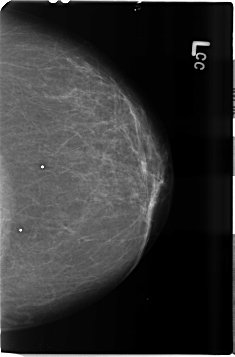

B_3506_1.LEFT_CC

LEFT_CC LINES 4632 PIXELS_PER_LINE 3048 BITS_PER_PIXEL 12 RESOLUTION 50 NON_OVERLAY